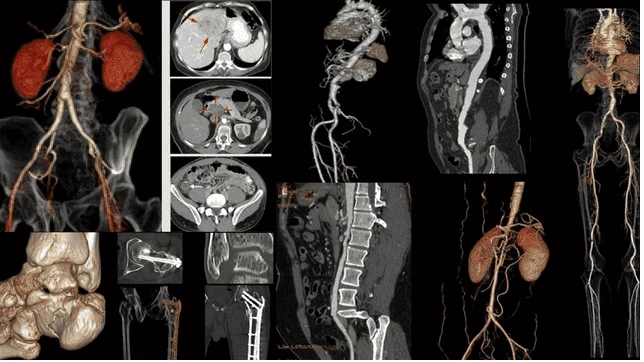

CT scan với khả năng tái tạo bộ phận, mô, xương trong cơ thể thông qua hình ảnh các lát cắt hoặc mặt cắt ngang của cơ thể cơ thể người chi tiết và chính xác, hỗ trợ bác sĩ phát hiện sớm các tổn thương dù rất nhỏ trong phổi mà các phương pháp như chụp X-quang không thể nhìn thấy

Hình ảnh học từ CT toàn thân giúp bác sĩ quan sát rõ tổn thương bên trong cơ thể mà mắt thường hay khám lâm sàng không thể thấy được

Hệ thống CT Scan được Bernard tận dụng triệt để trong tầm soát và phát hiện sớm các tổn thương lành tính; Tổn thương tiền ung thư (phổi, gan, vú, giáp, cổ tử cung, dạ dày, đại trực tràng,...); Ung thư giai đoạn sớm và ung thư (trích xuất từ hệ thống PACS tại Bernard)

Ngoài khả năng phát hiện ung thư phổi, CT Scan còn giúp phát hiện các bất thường trong ổ bụng với độ chính xác 95%. Các bác sĩ sử dụng CT để phân tích gan hoặc tuyến tụy, túi mật, bàng quang, khối u thận - Viêm đại tràng, viêm ruột, viêm ruột thừa - Sỏi thận, sỏi bàng quang, các tổn thương nội tạng (trích xuất từ hệ thống PACS tại Bernard)

Hình ảnh CT Scan trên hệ thống AI PACS tại Bernard